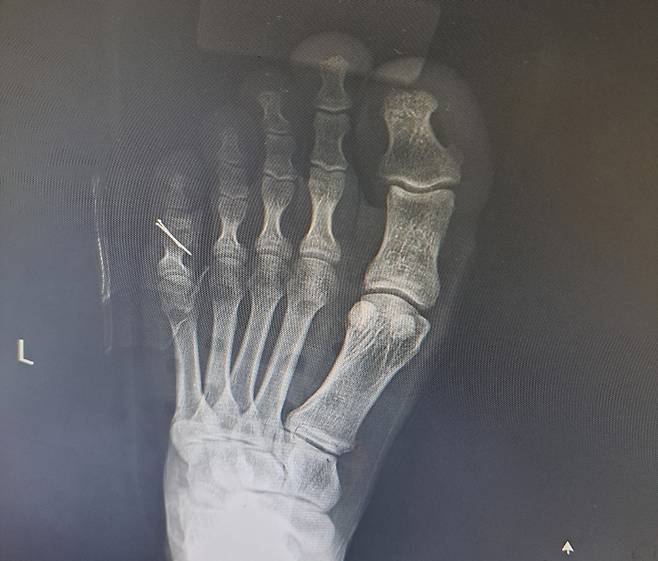

![철심 박은 B 병장 발 [A씨 제공. 재판매 및 DB 금지]](https://img3.daumcdn.net/thumb/R658x0.q70/?fname=https://t1.daumcdn.net/news/202407/04/yonhap/20240704092805848cznu.jpg)

전치 6주를 진단받은 B 병장은 다음날 바로 수술에 들어갔고, 인대와 뼈를 고정하기 위해 철심을 박는 수술을 받았다.